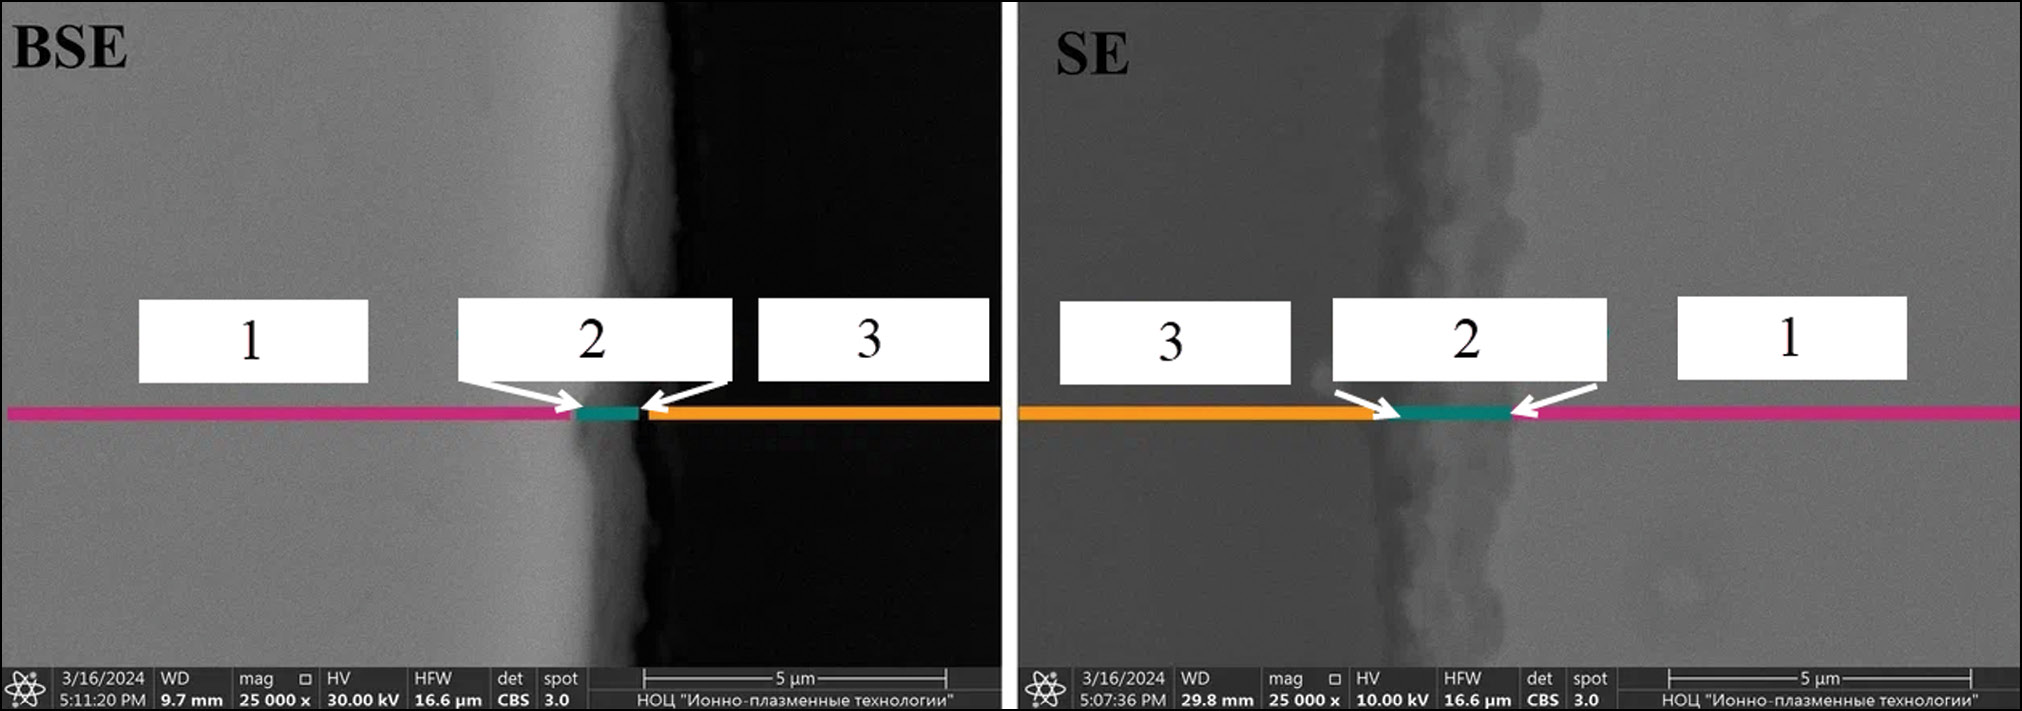

На рис. 2 представлены электронные фотографии шлифа сетки в режимах обратно рассеянных электронов (backscattered electrons, BSE) и вторичных электронов (secondary electrons, SE). На них видны области металлической сетки, собственно покрытия, а также смолы, в которую заливался образец, прежде чем подвергаться полировке. Отчётливо видно, что нанесённое покрытие хорошо контрастируется от металлической основы благодаря своему несколько более тёмному цвету. Толщина нанесённого покрытия составляла в среднем ≈1,0–2,0 мкм на разных участках образца. Растрескивания, точечных или протяжённых дефектов, а также отслаивания покрытия от подложки обнаружено не было.

Рис. 2. Электронные фотографии шлифов сеток с покрытием в режимах визуализации BSE и SE: 1 — титановая сетка, 2 — оксидное покрытие, 3 — смола.

Fig. 2. Electronic photographs of coated mesh sanding in BSE and SE visualization modes: 1 — titanium mesh, 2 — oxide coating, 3 — resin.

Покрытие титановых сеток методом микродугового оксидирования является перспективным методом обработки данных имплантатов, так как этот метод позволяет добиться получения равномерного оксидного покрытия (в реализованном случае ≈1,0–2,0 мкм), что было доказано с помощью электронной микроскопии. Как показано с помощью рамановской спектроскопии, в структуре покрытия детектируется биосовместимая фаза TiO2 (анатаз) без обнаружения значительного количества других соединений, в том числе токсических. Добавка в электролит нанодисперсного ГАП приводит к насыщению поверхности следовыми (на фоне подложки) количествами Ca и P, высвобождение которых в процессе имплантации может дополнительно способствовать остеоинтеграции. При этом сохраняется сетчатая структура имплантата (наличие исходной перфорации поверхности), стимулирующая клеточную пролиферацию тканей in vivo. Реализованный метод также не приводил к возникновению следов отслаивания покрытия, микротрещин, образованию острых краёв, которые потенциально могли бы травмировать окружающие ткани.